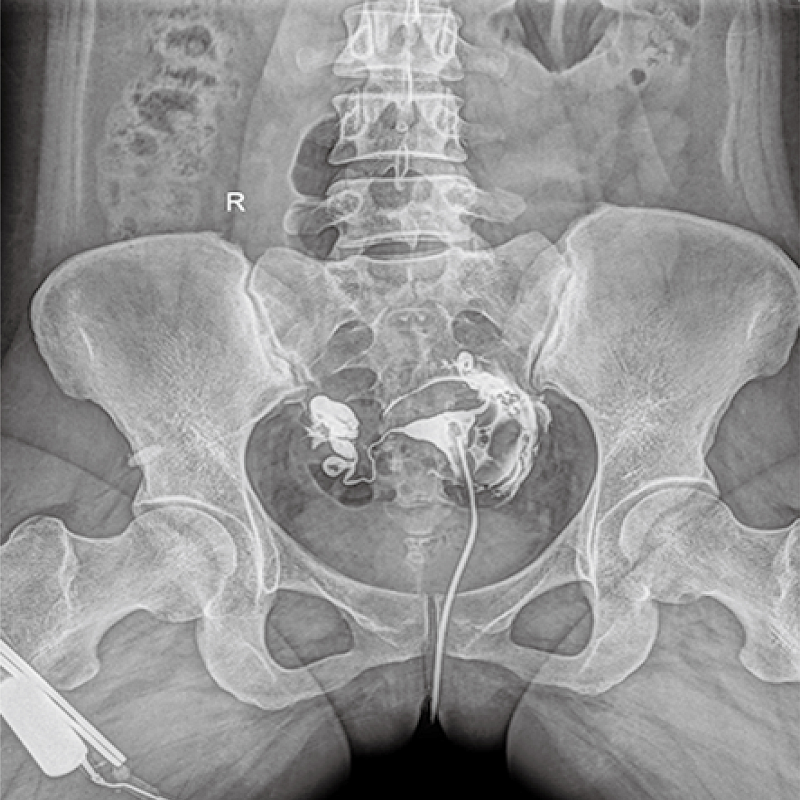

多功能、全視角、真視界,全面突破傳統(tǒng)X線攝影透視理念,通過一塊新型動態(tài)平板探測器,在檢查中既可實現(xiàn)數(shù)字透視又可實現(xiàn)數(shù)字?jǐn)z影,還可做數(shù)字胃腸及數(shù)字造影檢查。

● 只需一塊動態(tài)平板探測器,高效輕松實現(xiàn)攝影、透視和造影功能,幾乎可以滿足醫(yī)院全科室